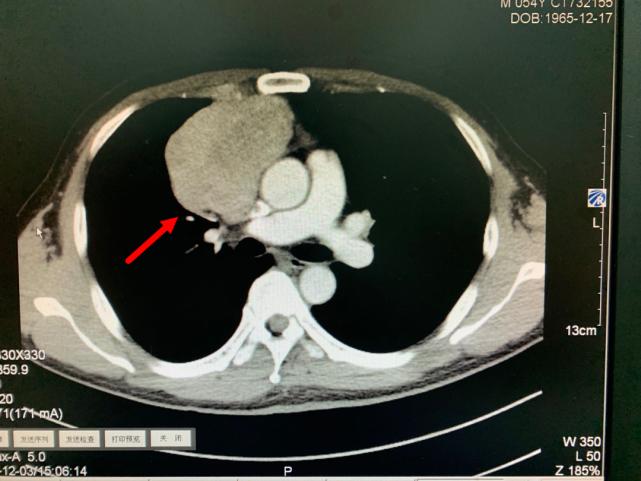

今年11月份,老方因“肠炎”在浙江省立同德医院肛肠科住院。“新冠”期间住院需要常规做胸部CT筛查,检查出来的结果却让他和医生们大吃一惊,胸部CT显示:胸腔内存在一个巨大肿瘤即纵膈肿瘤,大小约10.0cm×6.5cm×7.0cm,大小和一个成人男性拳头差不多。肿瘤紧靠着肺部、心脏及大血管,且与部分大血管有粘连,对重要的脏器已经造成了挤压。在确定胃肠道没有严重病患后,老方被转入心胸外科进一步作检查、治疗。

箭头所指为巨大纵隔肿瘤

叶中瑞主任医师通过进一步增强CT检查发现,老方体内的肿瘤巨大、与相邻的重要脏器粘连,界限不清,手术难度较大,且微创手术不合适,于是采取正中劈开胸骨的手术方式。手术过程顺利,术后恢复良好。第二天即下床活动。术后病理结果显示:纵膈肿瘤性质为中度恶性的胸腺肿瘤,后续还需要做进一步的放射治疗,以防止复发。老方在庆辛之余,他告诉叶中瑞主任医师,自己从今年开始每年都按时做体检,争取做到疾病早发现、早治疗,避免错过疾病的最佳治疗时机。